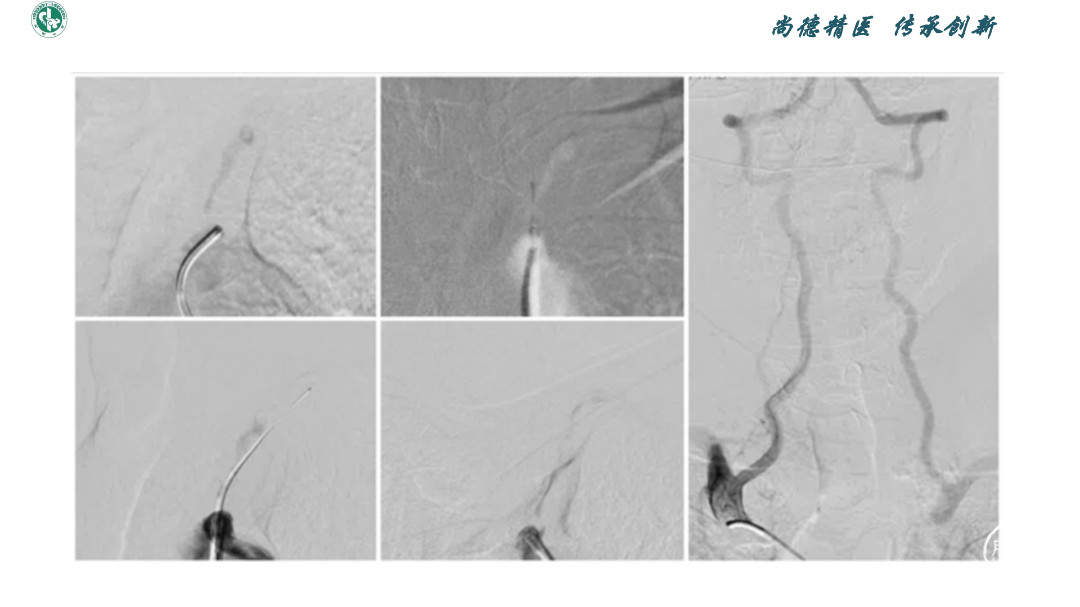

弓上血管狭窄的介入技术

赵宝元

武威市中医医院